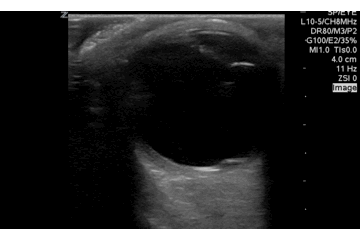

QA of the Day, Sono Stuff QA of the Day. Ocular movements for retinal detachment #POCUS #foamus #foamed Date: October 4, 2016Author: Mike 0 Comments Want to identify more subtle retinal or vitreous detachments? Evaluate with ocular movements. Share this: Share on X (Opens in new window) X Share on Facebook (Opens in new window) Facebook Like Loading...